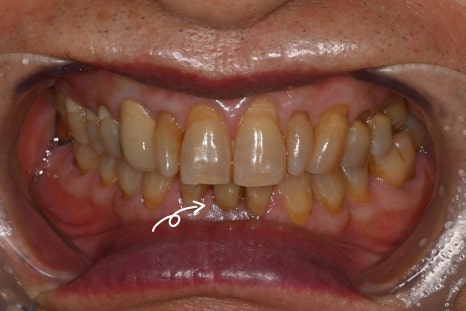

Photo with the final prosthesis placed 3 months after surgery

Three months after surgery, the final prosthesis was also placed,

and all treatment was completed.